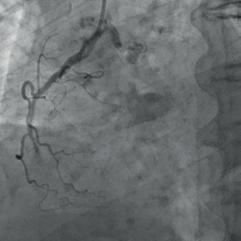

The patient was admitted to the intensive care unit with findings consistent with a diagnosis of NSTEMI. The onset of symptoms was one day prior. Previous medical history included arterial hypertension, dyslipidaemia and positive family history of cardiovascular disease. The electrocardiogram performed on admission was unremarkable except for the presence of a Q wave and a negative T wave in lead III. Laboratory tests revealed an elevated level of high-sensitivity troponin level (938, reference range 0 – 14 ng/L). Invasive coronary angiography revealed two-vessel disease with borderline (50 – 60 %) stenosis of the mid-LAD and a severely calcified, totally occluded right coronary artery (RCA) (Fig. 1).

Figure 1: Initial appearance of the RCA in the LAO view. Figure 2a: RCA dilatation with